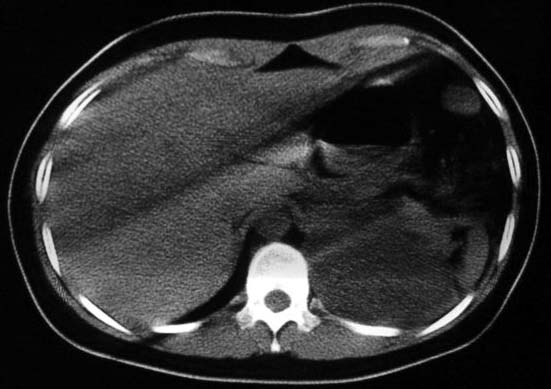

标题: CT5517:女性、24岁,反复胸痛、气促不能平卧半月。 [打印本页]

标题: CT5517:女性、24岁,反复胸痛、气促不能平卧半月。

左肺可见二个含气或液气的囊状影,左肺段支气管、左肺动脉显示不清,纵隔右移,考虑:左肺支气管肺囊肿,左肺发育不良,纵隔疝。

左侧气液腔与胃腔影相连,考虑膈疝。钡餐检查有助于诊断。

我看这是膈疝,在纵隔窗第六\\七幅图像上可见胃粘膜影,再者可见两个腔影,这在液气胸是不会有的.

支持膈疝,纵隔窗内可见消化道的内容物。

“反复胸痛、气促不能平卧半月”。+影像学表现=膈疝

液气胸 怎么会有2 个大腔?

还是个膈疝